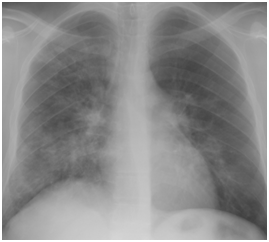

Graft failure occurred in 2 patients; one of them had already high serum creatinine at diagnosis (3mg/dl) and started dialysis 1year after H1N1 infection while the other has normal serum creatinine at diagnosis (1mg/dl) and was presented 1year later due to unexplained graft dysfunction. Some authors believe that influenza virus is capable of activating immunologic mechanisms leading to allograft rejection.9 The activation of such immunological mechanisms is related to production of interleukin -1, TNF, IL-6 and IL-8 during viral replication.10 The time interval for incidence of H1N1 infection started from the second half of December till the second half of January. Other series documented the incidence between the second half of July up to September in Asia (Singapore)8 while the largest number of confirmed cases of 2009 influenza A (H1N1) infection in North America occurred between March and July 2009.11 H1N1 infections has many complications in RTR including respiratory, cardiac and CNS sequences. However, the most common prescribed complication among RTR in the literature is respiratory complications. In one of early reports described 2 RTR that developed hypoxic respiratory failure and necessitated noninvasive ventilation12 while Singapore report described 2 mortalities among 10 cases of pneumonia.8 Other complications included H1N1 related myocarditis13 or encephalitis.14 In our series, only respiratory complications were encountered as previously mentioned. Our cases have excellent prognosis, most probably due to early initiation of oseltamivir therapy, doubling the dose and extension of the duration of treatment. Also temporary reduction of anti-proliferative drug may help RTR to recover early. Three cases of pneumonia showed inconclusive CXR while CT chest revealed bilateral infiltrates and this signifies the importance of CT chest in diagnosis of pneumonia in immune-compromised patients see Figure 3. Serial CXR was carried out to follow up lung recovery in cases of H1N1 pneumonia and it was correlated with the clinical response (Figure 4). The suspected number of RTR in December -2009 was 36 RTR which is double the number of suspected number in December-2010,this may be due to two facts; the first is vaccination with seasonal and novel H1N1 vaccine while the second is familiarity of criteria of diagnosis which reduced the number of suspected RTR.

Figure 3 Radiological diagnosis of H1N1 pneumonia in a 40-year-old female renal transplant recipient who suffered from fever and dyspnea of 2 days duration.